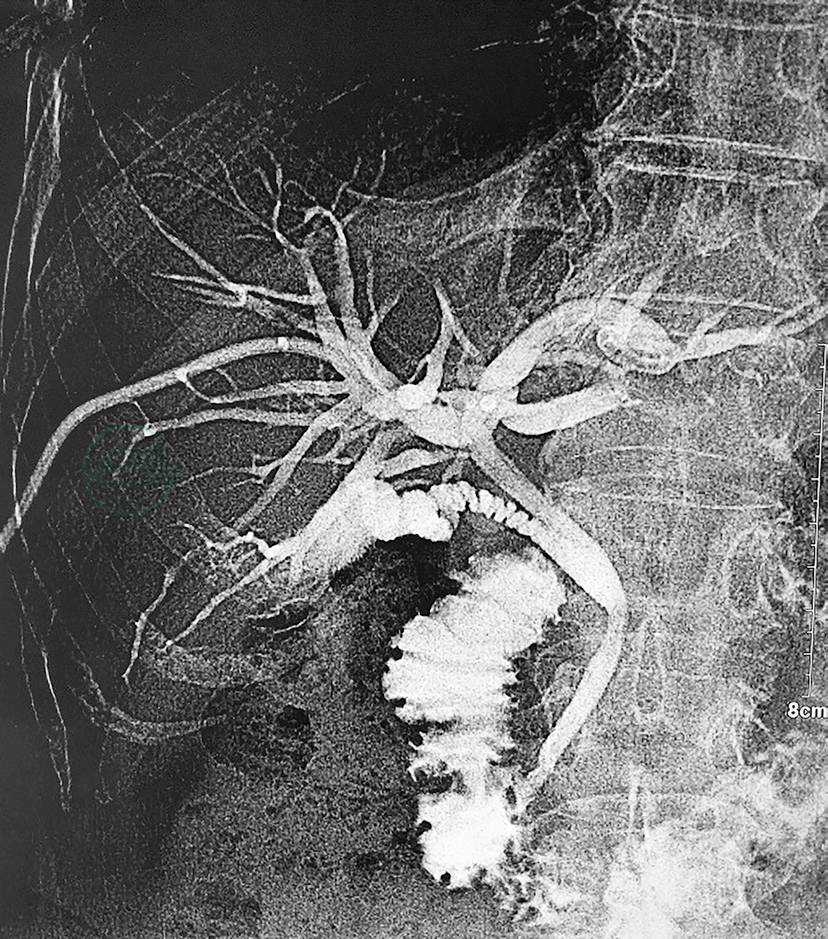

入院后患者因瘙痒严重,要求外引流减黄治疗,给予经皮肝穿刺胆道引流(percutaneous transhepatic cholangial drainage,PTCD)外引流,造影提示胆管肝门汇合部狭窄,导丝不能通过,于右肝留置引流管,肝内胆管呈腊肠样扩张(图2)。引流后1周,总胆红素由440μmol/L,降至300μmol/L。涎腺超声检查:左侧大小约2.2cm×1.2cm,右侧大小约2.3cm×0.7cm,双侧颌下腺结构不清,回声不均。IgG4结果回报:2.84g/L。

图2 PTCD造影